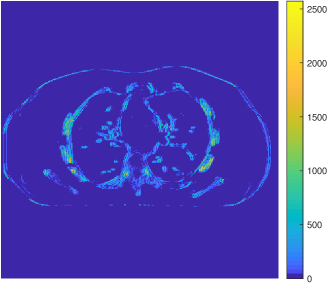

Fig. 2 (first column) shows three voxel-level classes (voxels are clustered by majority vote among patches overlapping them) for the reconstructed central axial slice. The top image only contains soft tissues, whereas the middle image shows some edges and bones in the vertical direction, and the bottom image captures some high-contrast structures. Fig. 2 (second column) shows the transforms for the corresponding classes. Each learned transform has 512 filters, and we show the first slice of 256 of these filters that show gradient-like and directional features.

Fig. 2 also shows the central axial slice of the sparse coefficient maps (volumes) for different filters of the transforms in the third, fourth and fifth columns. Each voxel value in a sparse coefficient map is obtained by applying the specific 3D filter to a 3D patch (whose front top left corner is at that voxel) and hard-thresholding the result. Coefficients for patches not belonging to the specific class are set to zero (masked out). The sparse code maps capture different types of image features (e.g., edges at different orientations or contrasts) depending on the filters and classes.

The sparse code vectors in (3) can be concatenated as columns of a sparse code matrix . Fig. 2 in [60] displays the axial slice of the sparse coefficient volume obtained from the 81st row of . This represents the effective map for the 81st filter of all classes (composed as the sum of the 81st filter’s map from each class). Fig. 12 shows the underlying maps for the 81st filter for all classes obtained by masking out (or setting to zero) pixels in Fig. 11 that correspond to patches not in the class. The filters are shown at the top left corner of the sparse coefficient images. Thus, in the ULTRA model, several filters with different properties and different features or edges collaboratively help form the “effective” sparse coefficient maps.

Here, we further illustrate the sparse coefficient maps generated by SPULTRA.